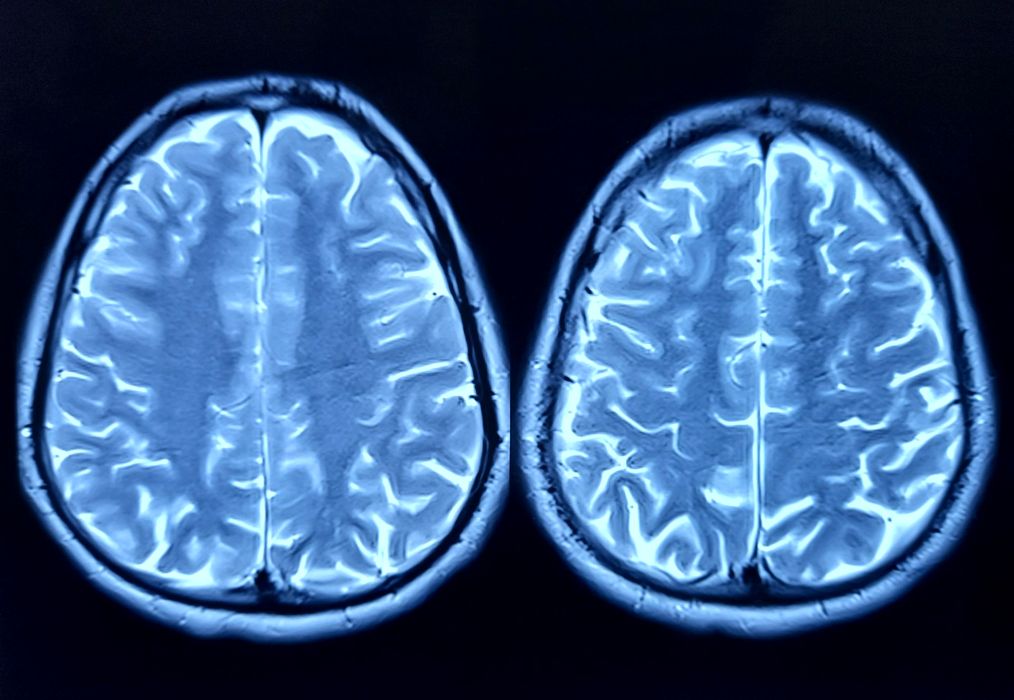

O nouă cercetare dezvăluie legătura dintre stres și dependență

O nouă cercetare dezvăluie legătura dintre stres și dependență. Momentele de stres îi împing adesea pe oameni spre obiceiuri precum consumul de alcool. Un studiu realizat la Universitatea Texas A&M (SUA) oferă o explicație clară: […]